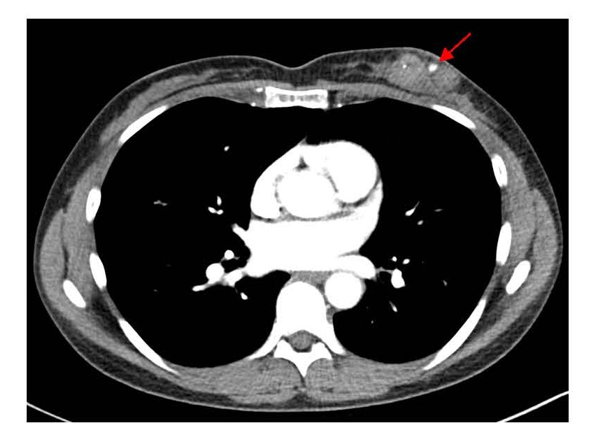

A 46-year-old woman with a past medical history of back pain, hypercholesterolemia, hypertension, migraines, and heart palpitations received a bilateral diagnostic mammography after self-palpating a left breast mass in January 2025. A new and suspicious 2–3 cm mass was visualized in the lower inner quadrant of the left breast, which corresponded to the palpable finding. Breast ultrasound confirmed the 2.6 cm irregular mass at the 7:00 position of the left breast, 2 cm from the nipple, and identified a left axillary lymph node with cortical thickening and hilar effacement suspicious for metastatic involvement. An ultrasound-guided CNB was performed 3 weeks after the patient initially palpated her breast mass. This was performed with three passes of a 9-gauge needle for histologic evaluation. Pathology demonstrated grade 3 invasive ductal carcinoma, triple-negative subtype (Estrogen Receptor (ER) 0%, Progesterone Receptor (PR) 0%, HER2- (IHC 1+; FISH ratio 1.2; HER2/cell 2.7), Ki-67 high, CK-19+, E-cadherin+). Further workup to delineate extent of disease included a breast MRI (magnetic resonance imaging), performed 1 week after her CNB, which estimated the biopsy-proven malignancy to be 4 cm and revealed multiple abnormal level 1 and 2 lymph nodes, and the presence of a PSA (Figure 1). Staging scans, including computerized tomography (CT) of the chest, abdomen, and pelvis (Figure 2), along with a bone scan, showed no evidence of distant metastatic disease. Preoperative chemoimmunotherapy with pembrolizumab per the KEYNOTE-522 regimen was recommended with breast ultrasound planned at 6 weeks to evaluate for PSA progression.

Figure 2. Axial contrast-enhanced chest CT showing enhancement with the left breast PSA. Focal hyper-density within the known carcinomamedial to the PSA corresponds with the biopsy marker. Key findings include outpouching of contrast from connected parented vessel and clear delineation of surrounding structures. CT: Computerized Tomography; PSA: Pseudoaneurysm.